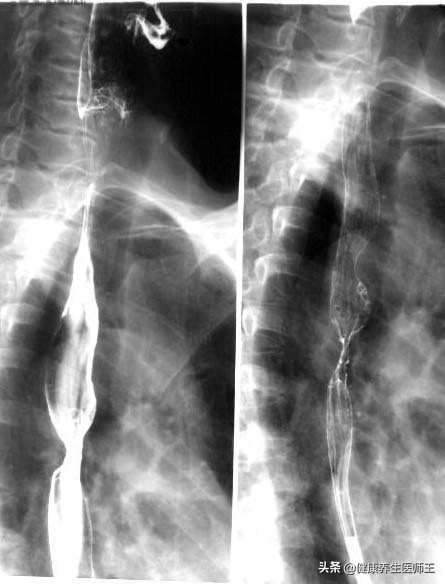

2.食管钡剂造影 当病人不宜行胃镜检查时,可选用此方法。钡剂造影主要表现为:

①黏膜皱襞做坏,代之以杂乱不规则影像:

②管腔局限性狭窄,病变处食管僵硬,近段食管扩张;

③不规则充盈。